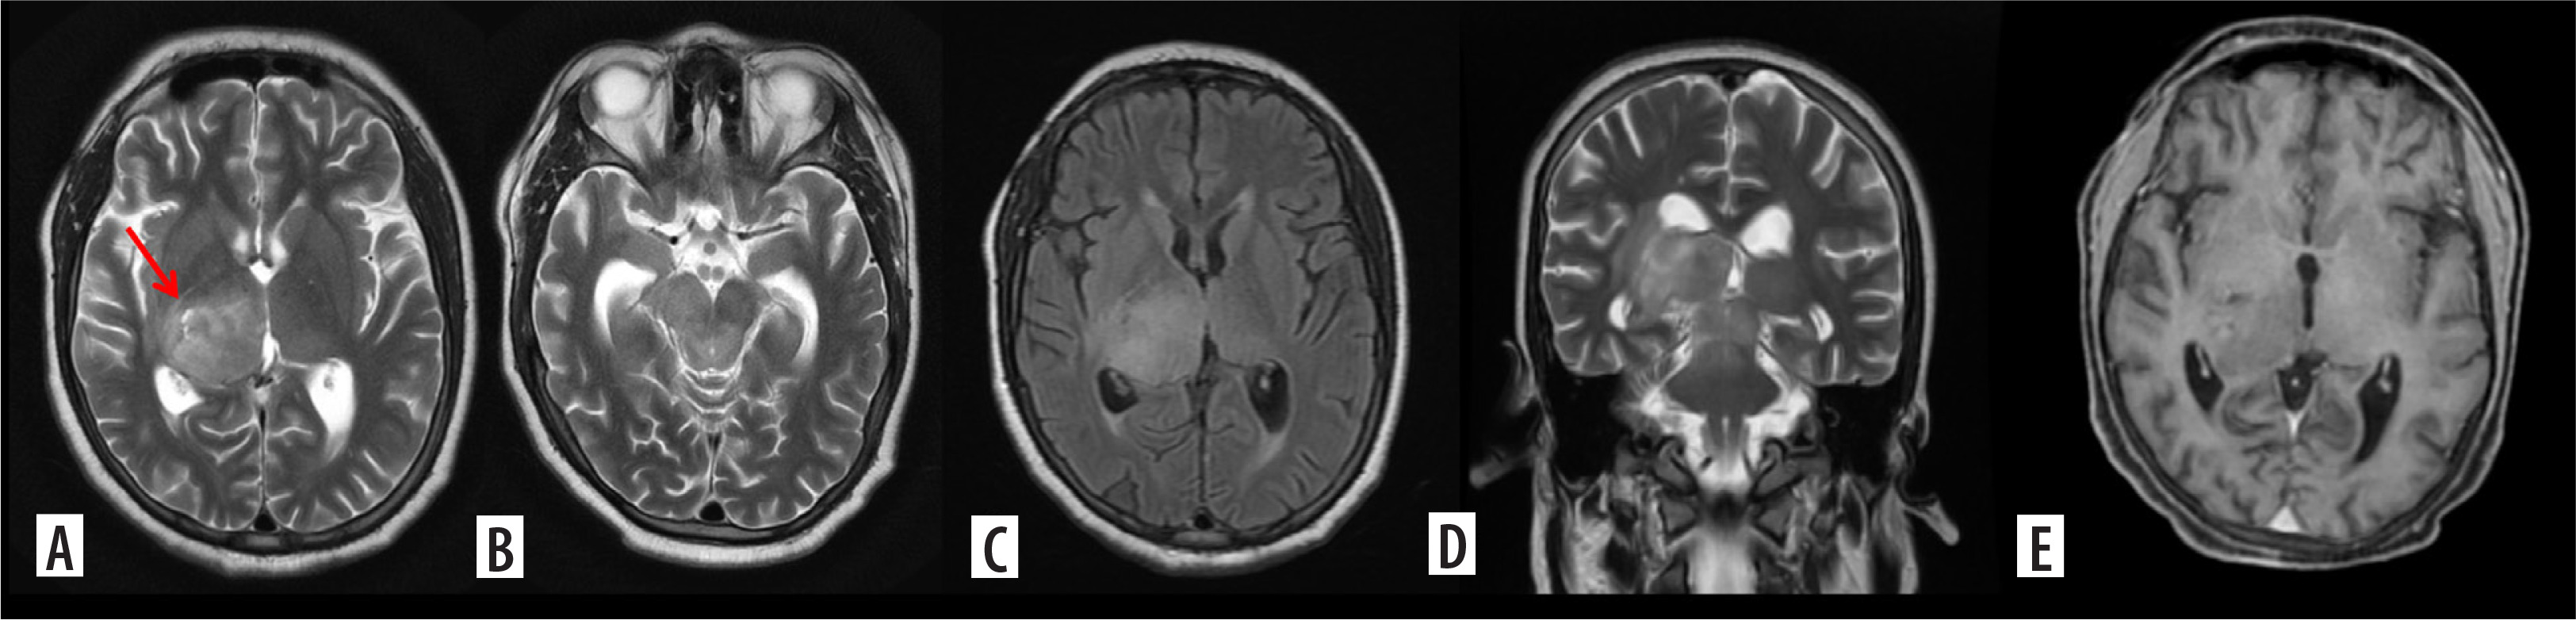

Figure 2

Glioblastoma. Axial T2, T2/FLAIR (A, B) and post contrast images (C) and coronal T2 (D) show a T2 intermediate lesion with intralesional necrosis in the right frontal lobe showing intense ring-like post contrast enhancement. Advanced magnetic resonance imaging evaluation with magnetic resonance spectroscopy shows absolute choline peak elevation with Ch:NAA 6.27 and Ch:Cr 3.42